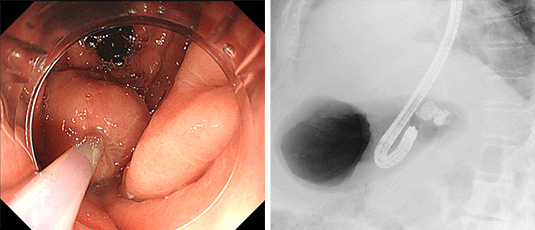

総胆管結石の場合はバスケットカテーテルやバルーンカテーテルなどの処置具を用いて結石を除去します。通常の処置具では除去困難な巨大結石に対しては、胆管の中に細径の内視鏡(経口胆道鏡)を挿入し結石を衝撃波で破砕する治療を行います。

巨大な総胆管結石

経口胆道鏡を用いて

衝撃波で破砕

結石除去後

総胆管結石や悪性腫瘍(膵癌、胆道癌)などによって胆道の流れが滞り、黄疸や感染がみられる場合はプラスチックや金属性のステントを胆管に挿入して胆汁の流れをよくします。

膵癌による胆管狭窄

胆管ステント留置後